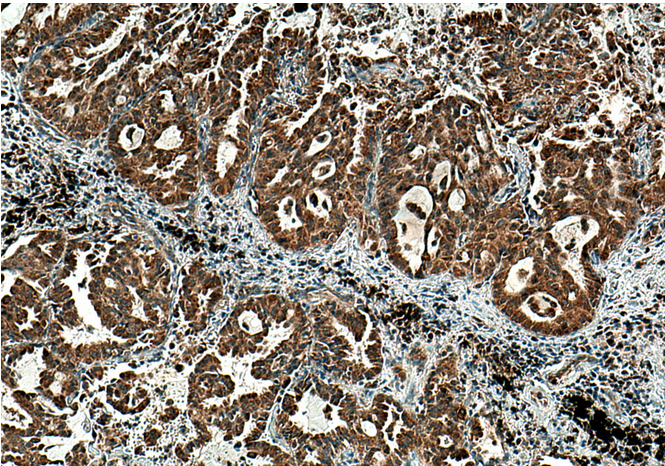

Immunohistochemical analysis of paraffin-embedded human lung cancer tissue slide using PSAT1 antibody at dilution of 1:200 (under 10x lens). Heat mediated antigen retrieval with Tris-EDTA buffer (pH 9.0).